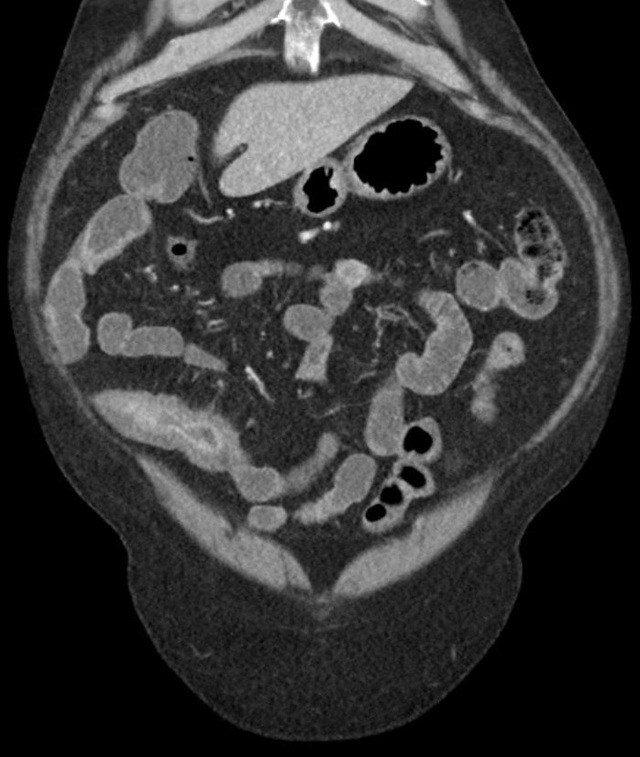

直到有一天,一位内科医生建议我进行一系列深入的检查。通过内镜检查和影像学检查,他们发现了肠道的异常炎症和穿透性病变,这些特征与克罗恩病的诊断标准高度吻合。那一刻,我的心情复杂难言,既有终于找到病因的释然,也有对未来治疗道路的担忧。

克罗恩病的诊断并非易事,它需要医生通过详细的临床症状观察、实验室检查和影像学检查来综合判断。对于我来说,这个过程是漫长而艰辛的,但也是我与。